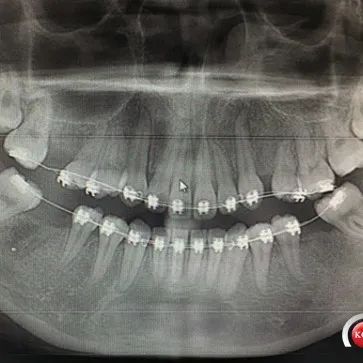

是的,有可能。智齿炎症可诱发肾病患者免疫异常激活,攻击肾脏组织,导致红细胞、尿蛋白的加重,一些患者也会出现血肌酐的异常升高。这种情况,需要及时找牙科医生进行抗炎处理,该使用抗生素可以用抗生素,牙科常用的比如头孢类(如头孢呋辛)、硝唑类(如甲硝唑)这些药物,肾友是可以按需使用的,肾毒性小。在抗炎处理,肾友的炎症反应彻底恢复后,通常尿检、血肌酐异常波动的情况可以恢复到原来水平,需要复查。对于经常牙齿发炎的患者而言,不要觉得就是上火,吃药对付过去就行了,应该找牙科看看坏牙,该怎么治怎么治,该拔除可以拔除。一些患者可能担心拔牙也算是个小手术,会有创伤,对肾不好。其实,这就是一个长痛短痛的问题,不拔的话,智齿经常发炎就对肾好了吗?反反复复的炎症,搞得肾病就没消停过,指标怎么容易好呢?...